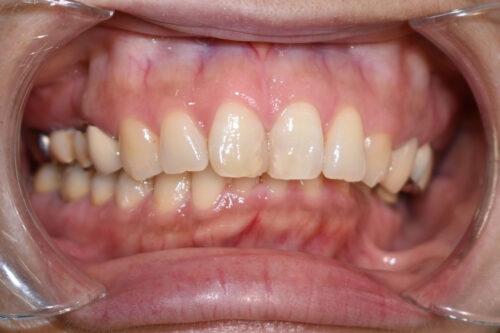

本症例では

左側の完全クロスバイトにより

顎が変形しておりましたが、

矯正治療単独の矯正治療でも

かみ合わせを 正しくすることで

臨床治療においては

お顔立ちの曲がりも 良くなることが多いです。